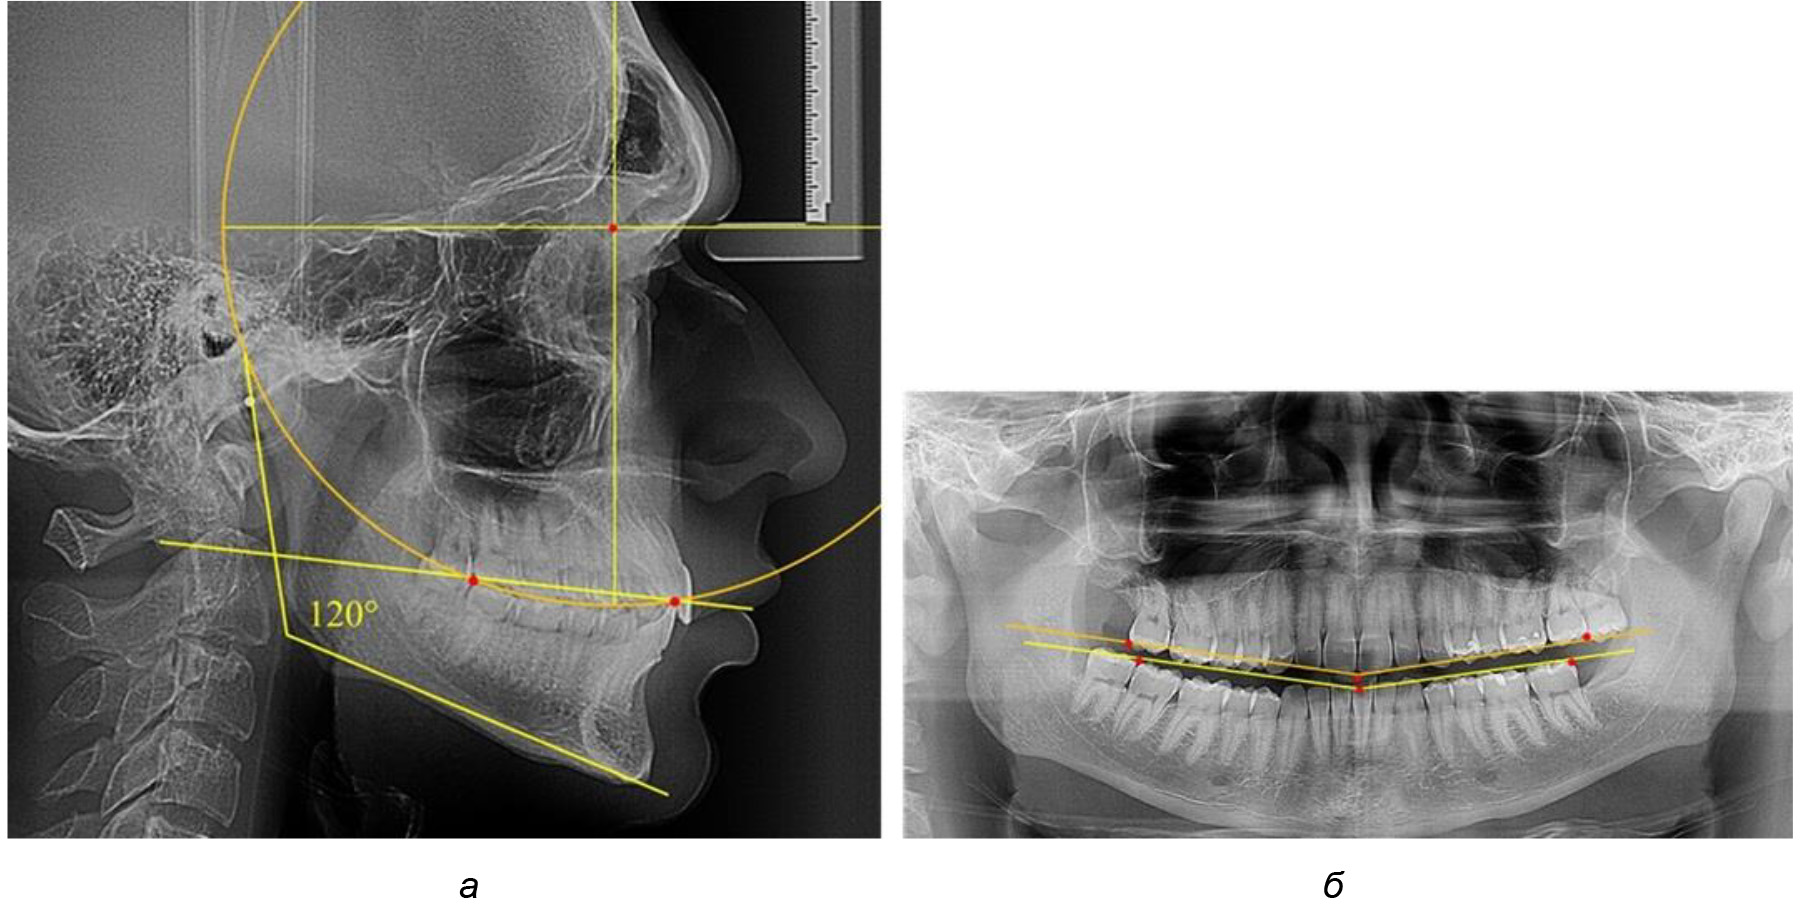

На рентгенограммах людей 2-й подгруппы (30 человек с нейтральным типом роста) величина угла нижней челюсти в среднем составила (120,34 ± 2,19) ° и характеризовала нейтральный тип нижней челюсти.

Глубина кривой Spee в среднем по 2-й подгруппе составил (3,54 ± 0,58) мм, что было незначительно меньше, чем при анализе аналогичного показателя 1-й подгруппы.

Достоверных различий с показателями, полученными при анализе ТРГ и ОПТГ, нами не отмечено (р ˃ 0,05). Деление величины радиуса круга к длине окклюзионной линии составило 1,612 ± 0,02, что, так же как и в 1-й подгруппе, было близким по значению к числу Фибоначчи (1, 618).

Рис. 3. Особенности кривой Spee на ТРГ (а) и ОПТГ (б) при нейтральном типе роста нижней челюсти